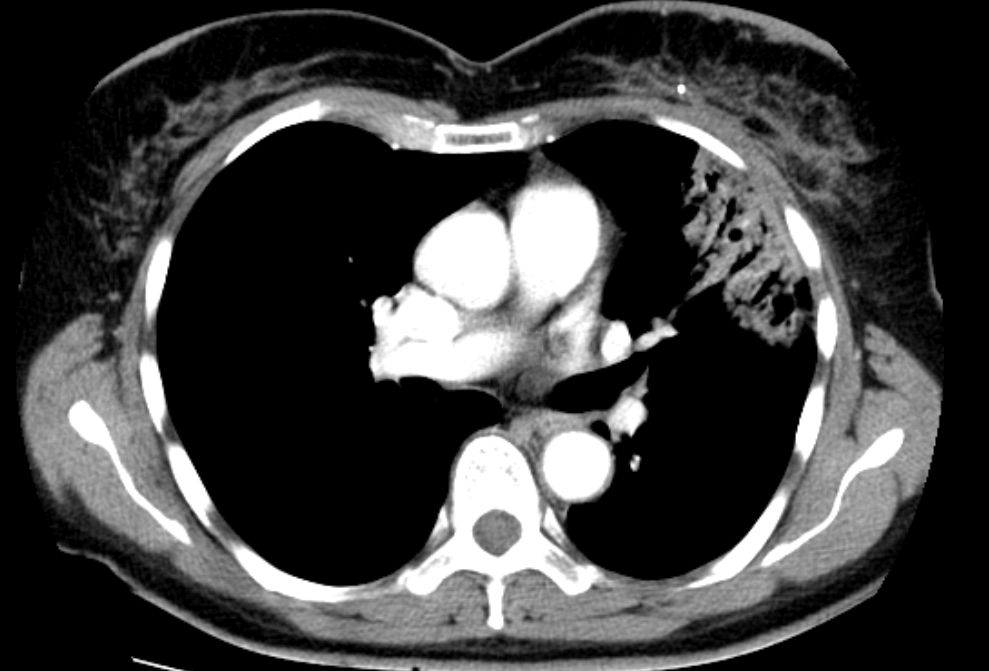

Pneumonitis 53-jährige Frau mit Mammakarzinom links. 3 Monate nach brusterhaltender Therapie und Bestrahlung der Brust wird die Patientin wegen einer Pneumonie ins Krankenhaus eingewiesen. Nach Gabe von Antibiotika zunächst nur geringe Besserung.

Das Thoraxbild zeigt ein Infiltrat im linken Mittelfeld.

Das CT zeigt eine Anschoppung direkt unter der bestrahlten Brust. Negatives Bronchogramm gut erkennbar.

Durch ein leichte Trichterbrust war ungewöhnlich viel Lungenparenchym in der Tangente bestrahlt.